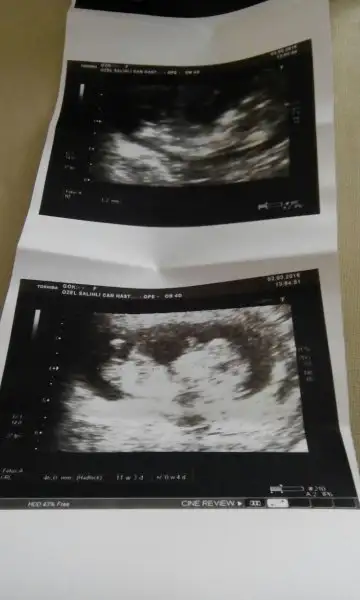

kızlar bana da yorum yapabilir misiniz ? 6+1 günlük

• IMG_4668.webp

IMG_4668.webp

11,3 KB · Görüntüleme: 88

• IMG_4667.webp

IMG_4667.webp

11,2 KB · Görüntüleme: 86